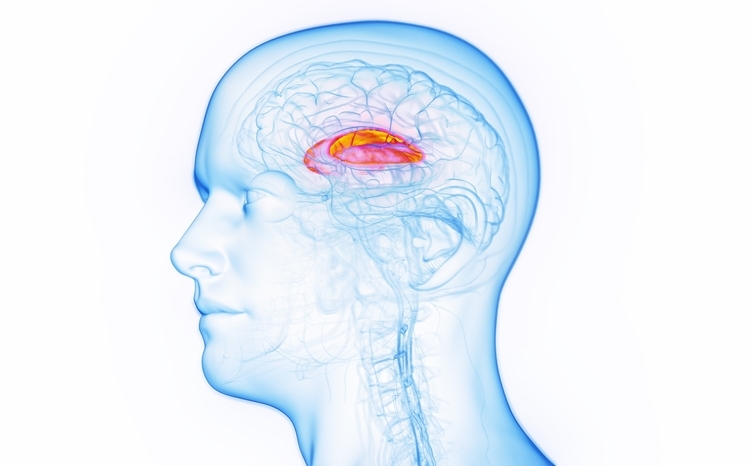

Tics are fast, repetitive muscle movements that result in difficult to control body movements or sounds. When both motor and vocal tics are present for more than one year, this is commonly known as Tourette syndrome.